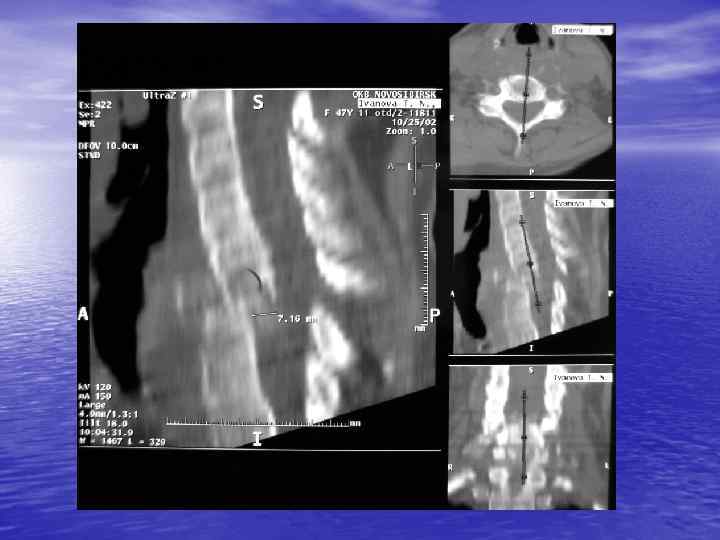

Структурный анализ Оценка основных макроскопических признаков: - положение - форма - размеры - характер контуров и структур патологически измененных участков

Структурный анализ